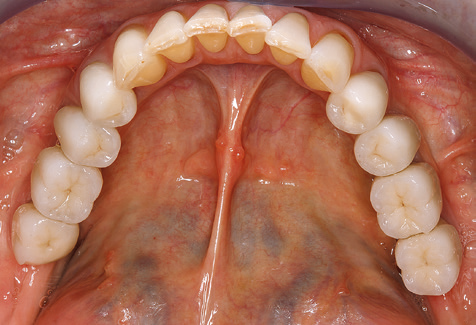

Standardised and regular risk-adapted care in the scope of SPT is the key to treatment success for the clinical long-term success in periodontically compromised patients. This is particularly true for patients fitted with implants following successfully completed periodontal treatment (Fig. 11a and b).

Due to the presence of periodontal disease, SPT was performed every three months in the first years following the insertion. The patient demonstrated a high degree of motivation and good compliance. The pocket depths recorded annually revealed a stable periodontal situation with a BOP index of below five per cent. On the basis of the stable periodontal situation and good cooperation on the patient’s part, the recall interval was extended to every six months as of the sixth year of the prosthetic function phase. Following the change in the recall interval, the respective annual documentation of the periodontal status continued to reveal a stable periodontal situation with no increase in the pocket depths and a BOP index below five per cent (Fig. 2a and b).

The patient continues to visit the clinic every six months for SIT. In the following, the patient is taken as an example for demonstrating the individual working steps in a structured SPT session as it has been performed with barely any modifications over the last 12 years. Of course, some new materials and devices have been integrated into the concept over the years. This clinical case report presents the current material and device concept.